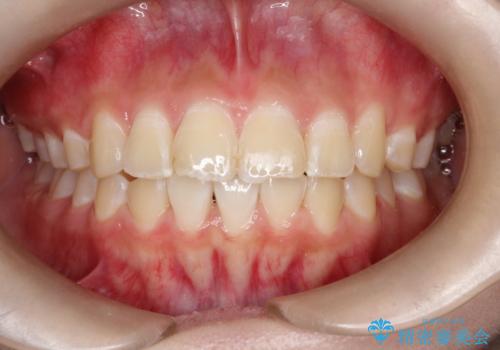

- 前歯が出ていることを主訴に来院されました。

インビザラインにて奥歯の遠心移動を行いながら最大限前歯が下がるように治療を行いました。

今回は遠心移動とIPRによってここまで前歯を下げることができました。